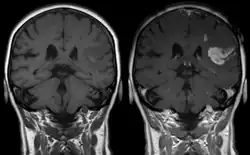

Magnetic resonance imaging

Gadolinium-based pharmaceuticals alter the relaxation time, and hence spectral line shape, of those protons that are in water molecules that are transiently attached to the paramagnetic atoms, resulting contrast enhancement of the MRI image.[12] This allows better visualisation of some brain tumours.[12]